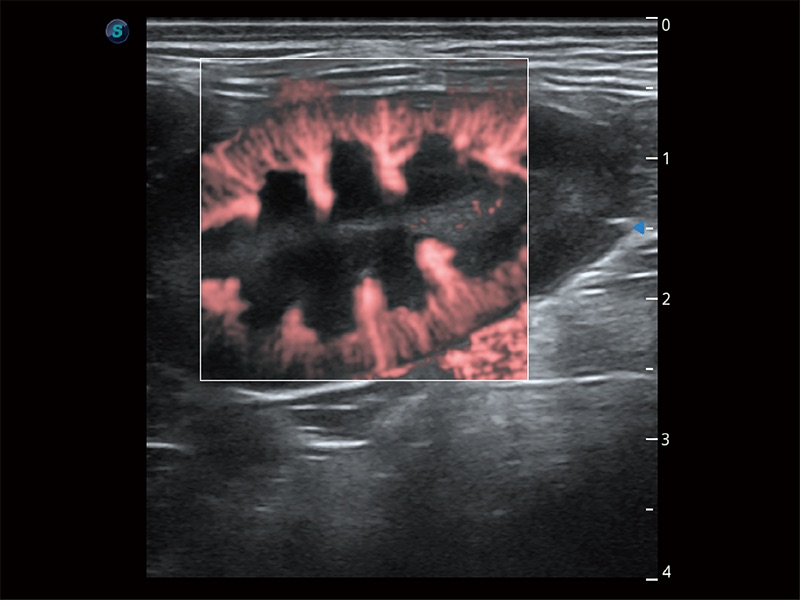

Ausgestattet mit dem gesamten Sortiment an Phased-Array-Schallköpfen von SonoScape (S1-5, 7P-A, 8P1), hochentwickelter Verarbeitungstechnologie und modernsten kardiologischen Tools bietet die ProPet-Serie Tierärzten eine umfassende ABklärung der Herz- und Myokardfunktionen.

Nutzt myokardiale Doppler-Frequenzverschiebungen zur Quantifizierung der myokardialen Gewebebewegung, wobei Rot und Blau die unterschiedlichen Bewegungsrichtungen der Herzwände darstellen. Durch die Kombination von TDI und PW lässt sich die Bewegungsbahn der Myokardwand besser erfassen.